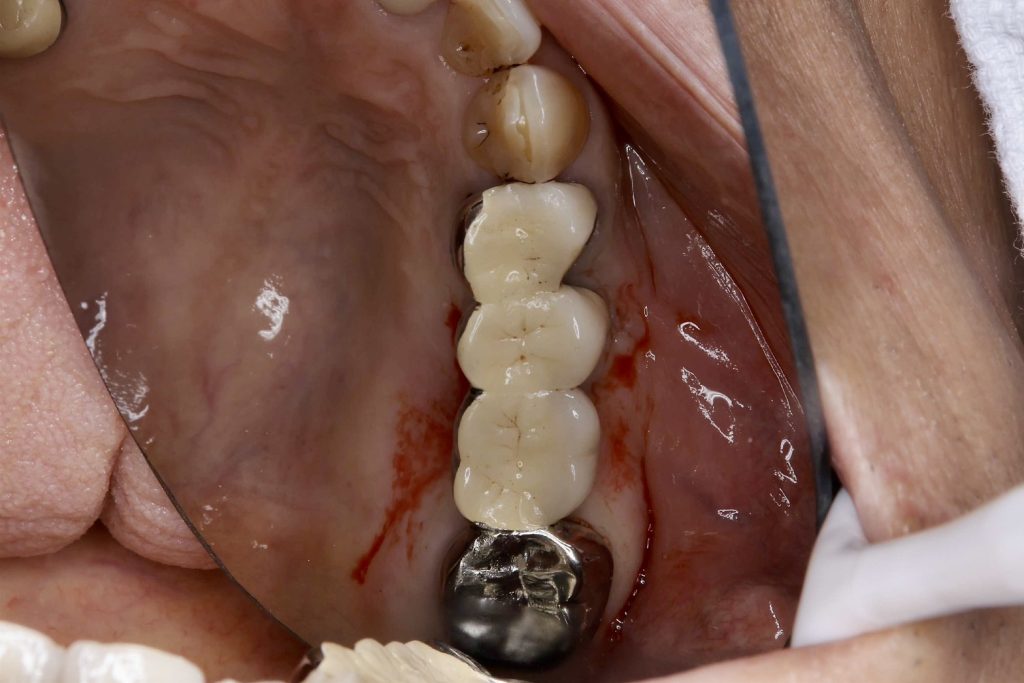

50代、男性、左上に違和感があることを主訴に来院され、インプラント治療を行いました。

| 診断結果 | 左上5番歯根破折 |

| 治療内容 | 抜歯即時インプラント |